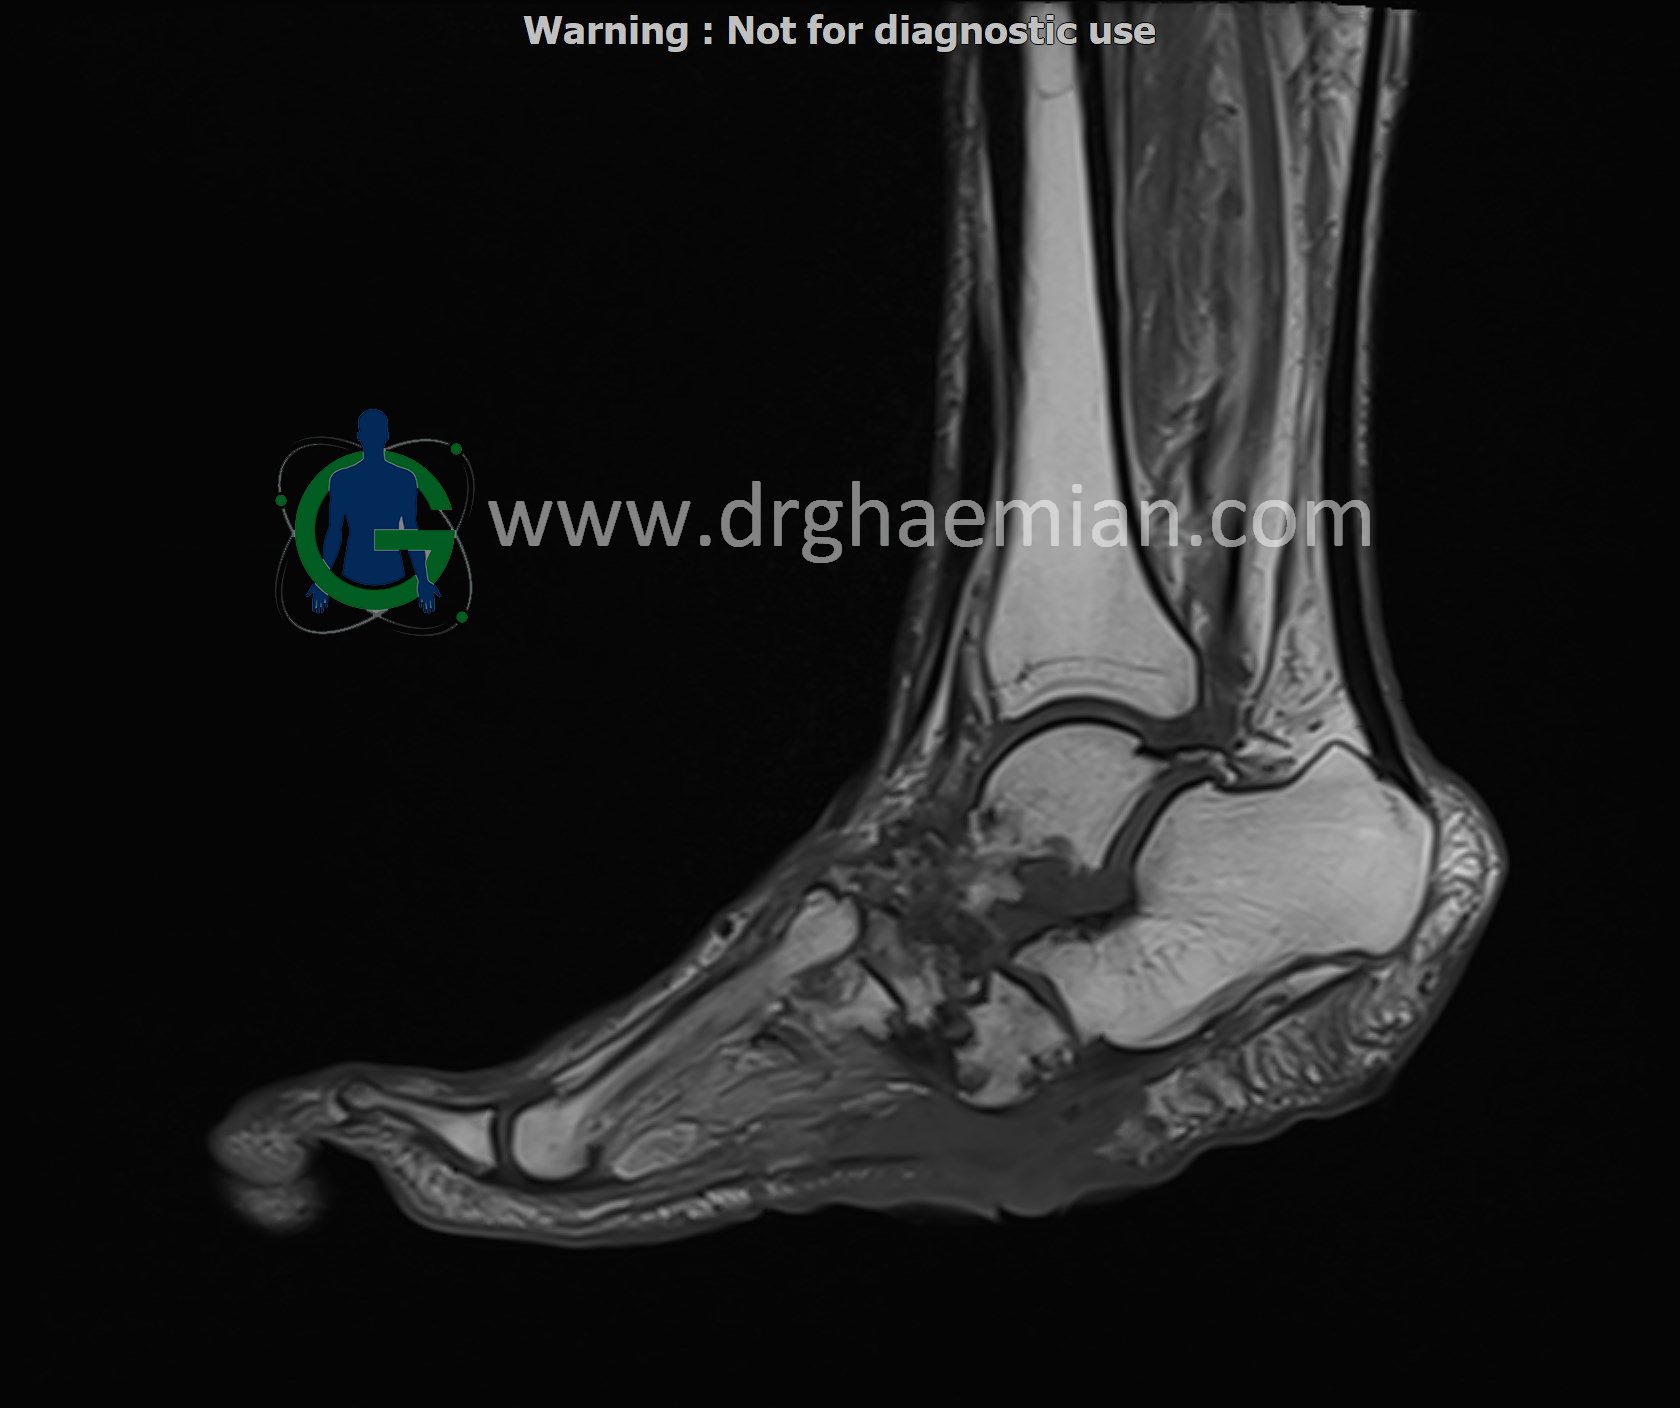

ام آر آی کف پا و انگشتان یک روش تصویربرداری پزشکی است که با استفاده از میدانهای مغناطیسی قوی و امواج رادیویی تصاویر دقیق و باکیفیتی از ساختارهای داخلی کف پا و انگشتان ایجاد میکند. این روش بدون استفاده از اشعههای مضر مانند اشعه ایکس انجام میشود و به پزشک کمک میکند تا با جزئیات بیشتری آسیبها، التهابها یا مشکلات دیگر را تشخیص دهد.در ان کیس یک پای بیمار مبتلا بهب بیماری دیابت دیده میشود.

MRI OF RIGHT FOOT

1.5 Tesla MR System

Multislice, multiplanar and multisequence MR images findings:

There is a skin ulcer in the plantar aspect of the foot, superficial to the midfoot, without obvious collection.

Destruction and erosion of the midfoot structures and articular spaces are seen, resulting in midfoot collapse.

T1 signal intensity of bone marrow in the midfoot region is preserved, and there is no imaging evidence of acute osteomyelitis; however, chronic osteomyelitis cannot be ruled out.

Abnormal high T2WI and low T1WI signal intensity are observed in the 5th proximal and distal phalanges, in association with a suspicious plantar site ulcer, highly suggestive of osteomyelitis in this area.

Other bones, joints, and soft tissues of the foot appear unremarkable.

Impression:

Plantar skin ulcer overlying the midfoot with no associated collection

Structural destruction and erosion of midfoot bones and articular spaces causing midfoot collapse, without definite signs of acute osteomyelitis, though chronic osteomyelitis cannot be excluded

Abnormal marrow signal changes in the 5th proximal and distal phalanges in association with a suspicious plantar ulcer, highly suggestive of osteomyelitis

No other abnormality detected